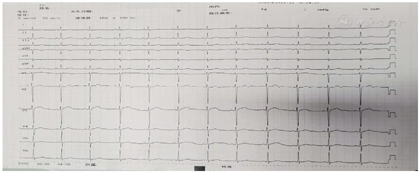

入院体格检查:脉搏72次/min,血压167/80 mmHg,四肢血压符合生理性规律,体质量指数23.1 kg/m2,神志清楚,颈静脉未见异常,双肺呼吸音清晰,双肺未闻及干湿性啰音,心界正常。心律齐,心率72次/min,各瓣膜听诊区未闻及明显杂音。腹部平坦,未及明显压痛、反跳痛、未闻及大动脉杂音,神经系统体格检查未及阳性体征。双下肢小腿胫侧皮肤可见色素沉着,双下肢无水肿。未见向心性肥胖,无满月脸及皮肤紫纹,无甲亢面容,性征发育正常。辅助检查:(2021年7月2日,玉溪市人民医院)皮疹处皮肤组织病检示非特异性炎症改变。心电图:窦性心律,电轴不偏,T波低平。血常规、电解质、BNP、肝肾功能、心梗三项、术前传染病、尿粪常规、凝血功能未见明显异常。炎症指标:C反应蛋白(超敏)97.81 mg/L↑;红细胞沉降率测定-仪器法:51 mm/h ↑。心肌酶:天门冬氨酸氨基转移酶12 U/L↓(正常范围13~35 U/L),乳酸脱氢酶258 U/L↑(正常范围120~250 U/L),肌酸激酶29 U/L↓(正常范围40~200 U/L),肌酸激酶同工酶15.90 U/L(正常范围0~25 U/L),α-羟丁酸脱氢酶200 U/L↑(正常范围44~148 U/L);血脂全套:甘油三酯2.04 mmol/L↑,总胆固醇5.67 mmol/L↑,低密度脂蛋白胆固醇3.62 mmol/L↑;甲状腺功能:三碘甲状原氨酸1.17 nmol/L,甲状腺素82.57 nmol/L,促甲状腺刺激激素0.334 mIU/L↓;免疫球蛋白E,免疫球蛋白定量4项,血清免疫固定电泳分析,抗中性粒细胞胞浆抗体,抗核抗体谱未见明显异常。2022年3月21日心脏超声(LA 24 mm,LV 46 mm,RA 16 mm),EF正常。动态心电图未见心律失常及ST-T异常。肾上腺CT增强平扫:左侧腹膜后(左肾静脉下方腹主动脉左旁)见软组织团块,边界清楚,大小约41 mm×46 mm×41 mmm,强化明显,双期CT值约148 HU,134 HU,双肾上腺形态,大小及强化未见异常。检查结论:左侧腹膜后富血供实性占位,考虑副神经节细胞瘤可能。肺部CT提示:肺部慢性炎症/纤维化灶。因患者外院已应用抗生素,当前无咳嗽、咳痰,本次住院暂未应用抗生素。高血压5项(卧位):促肾上腺皮质激素,醛固酮/肾素比值(卧位),血管紧张素Ⅱ(卧位),皮质醇均正常,醛固酮-卧位355 pg/ml(正常范围10~160 pg/ml),肾素-卧位118.7 pg/ml(正常范围4~24 pg/ml)。高血压5项(立位):促肾上腺皮质激素,醛固酮/肾素比值(立位),血管紧张素Ⅱ(立位),皮质醇均正常,醛固酮-卧位587 pg/ml(正常范围40~310 pg/ml),肾素-卧位294.3 pg/ml(4~38 pg/ml)。儿茶酚胺3项:多巴胺及肾上腺素阴性,去甲肾上腺素21 611 pmol/L(414~4435 pmol/L)。24 h尿液儿茶酚胺:肾上腺素阴性,去甲肾上腺素大于5 734 nmol/24 h(正常范围68~378 nmol/24 h),多巴胺5 198(正常范围655~3 425)。详见图1,图2,图3,图4。